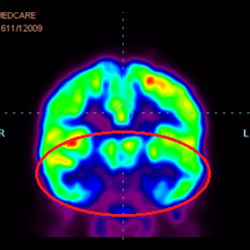

細(xì)胞治療后,藍(lán)色和黑色區(qū)域減少,并且看到更活躍的區(qū)域。這表明損傷減少并改善了大腦功能。

這證明細(xì)胞療法是治療腦癱兒童安全有效的方法。細(xì)胞療法可以更新大腦損傷的核心,并且可以通過 PET CT 掃描來監(jiān)測大腦的改善情況。這些細(xì)胞療法與標(biāo)準(zhǔn)治療一起促進(jìn)腦癱兒童的生長和改善。